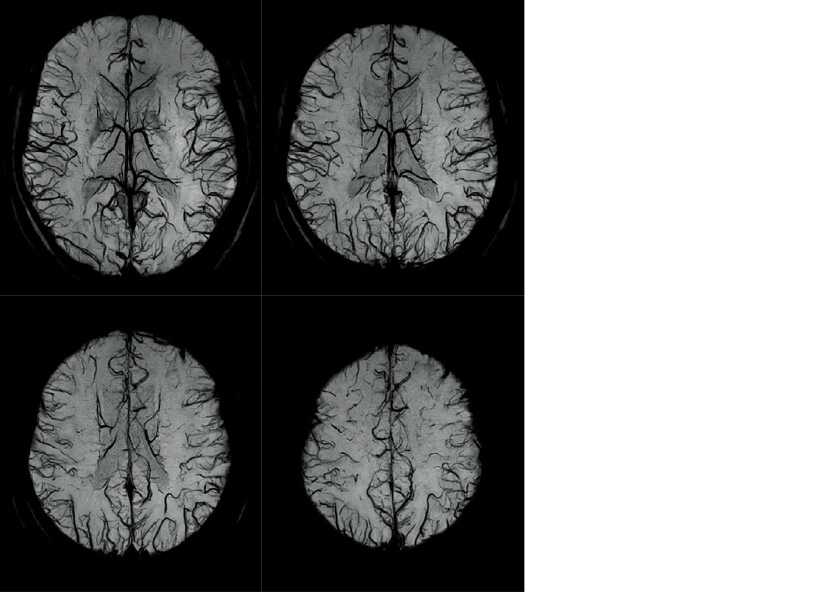

Effects of RADAR in TOF MRA and GrE T2*WI

RADAR has been applied to GrE sequences using a high-precision signal correction technology. This has enabled the combined use of RADAR in all sequences required for routine head examinations.

High-speed, high-resolution 3D T2*WI imaging is used to acquire images that sensitively reflect differences in magnetic susceptibility.

Our BSI offers high-speed imaging due to EPI measurement.

Venous blood and hemorrhage cause loss of signals in T2* images due to BOLD (blood-oxygen level dependent) effects. BSI performs minimum intensity projection (minIP) processing and superimposes phase information to further increase the contrast of images.

Examples of BSI (minP) images